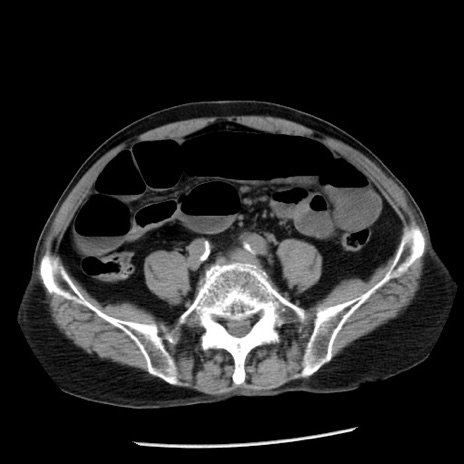

症例26(横断像)

【症例】80歳代男性

【主訴】嘔吐

【現病歴】昨晩2回嘔吐あり、今朝になっても嘔吐あり。来院。

【既往歴】胃潰瘍

【身体所見】意識清明、BT 37.6℃、BP 166/95mmHg、HR 100bpm、SpO2 97%、腹部:平坦・軟、腸蠕動音聴取良好、圧痛なし。

【データ】WBC 21900、CRP 1.46